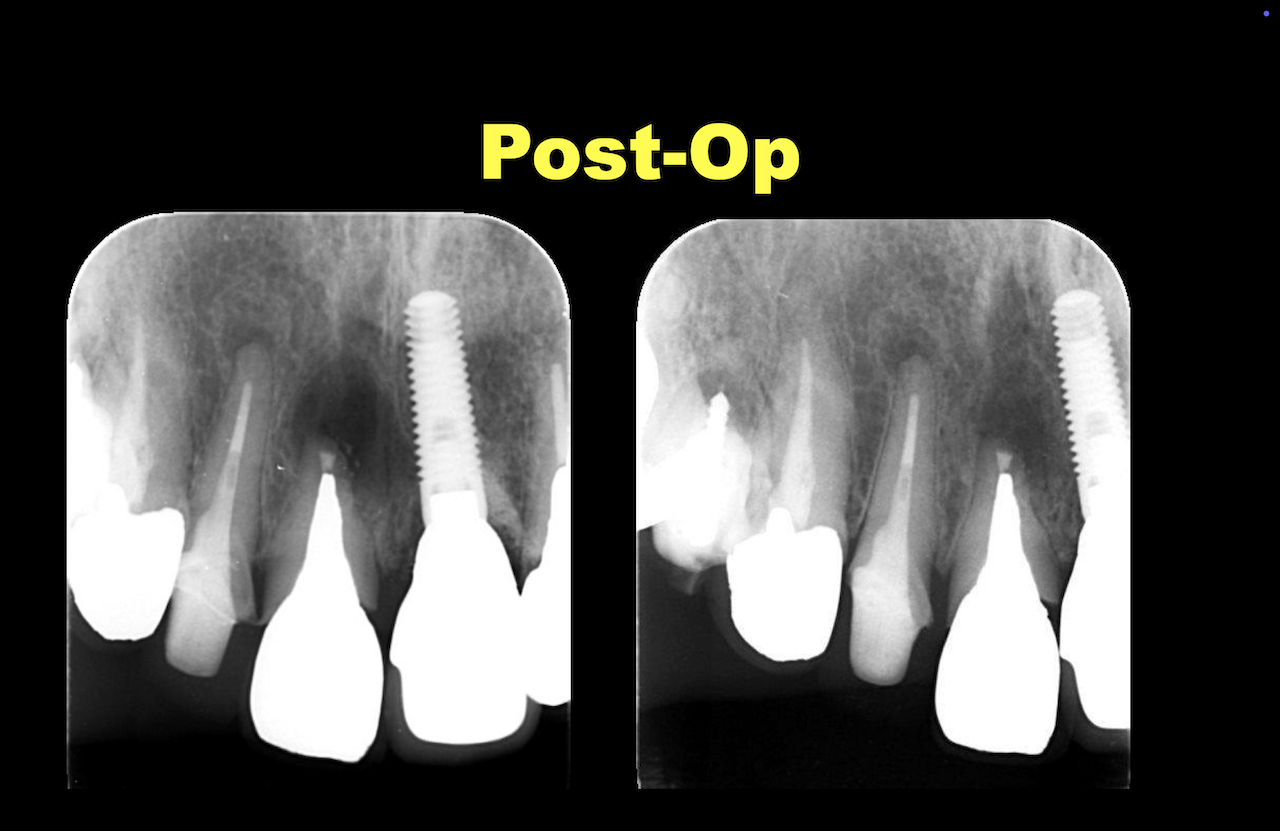

この絵を元に以下のようにApicoectomyを行う。

ここから1年経過して以下のようになった。